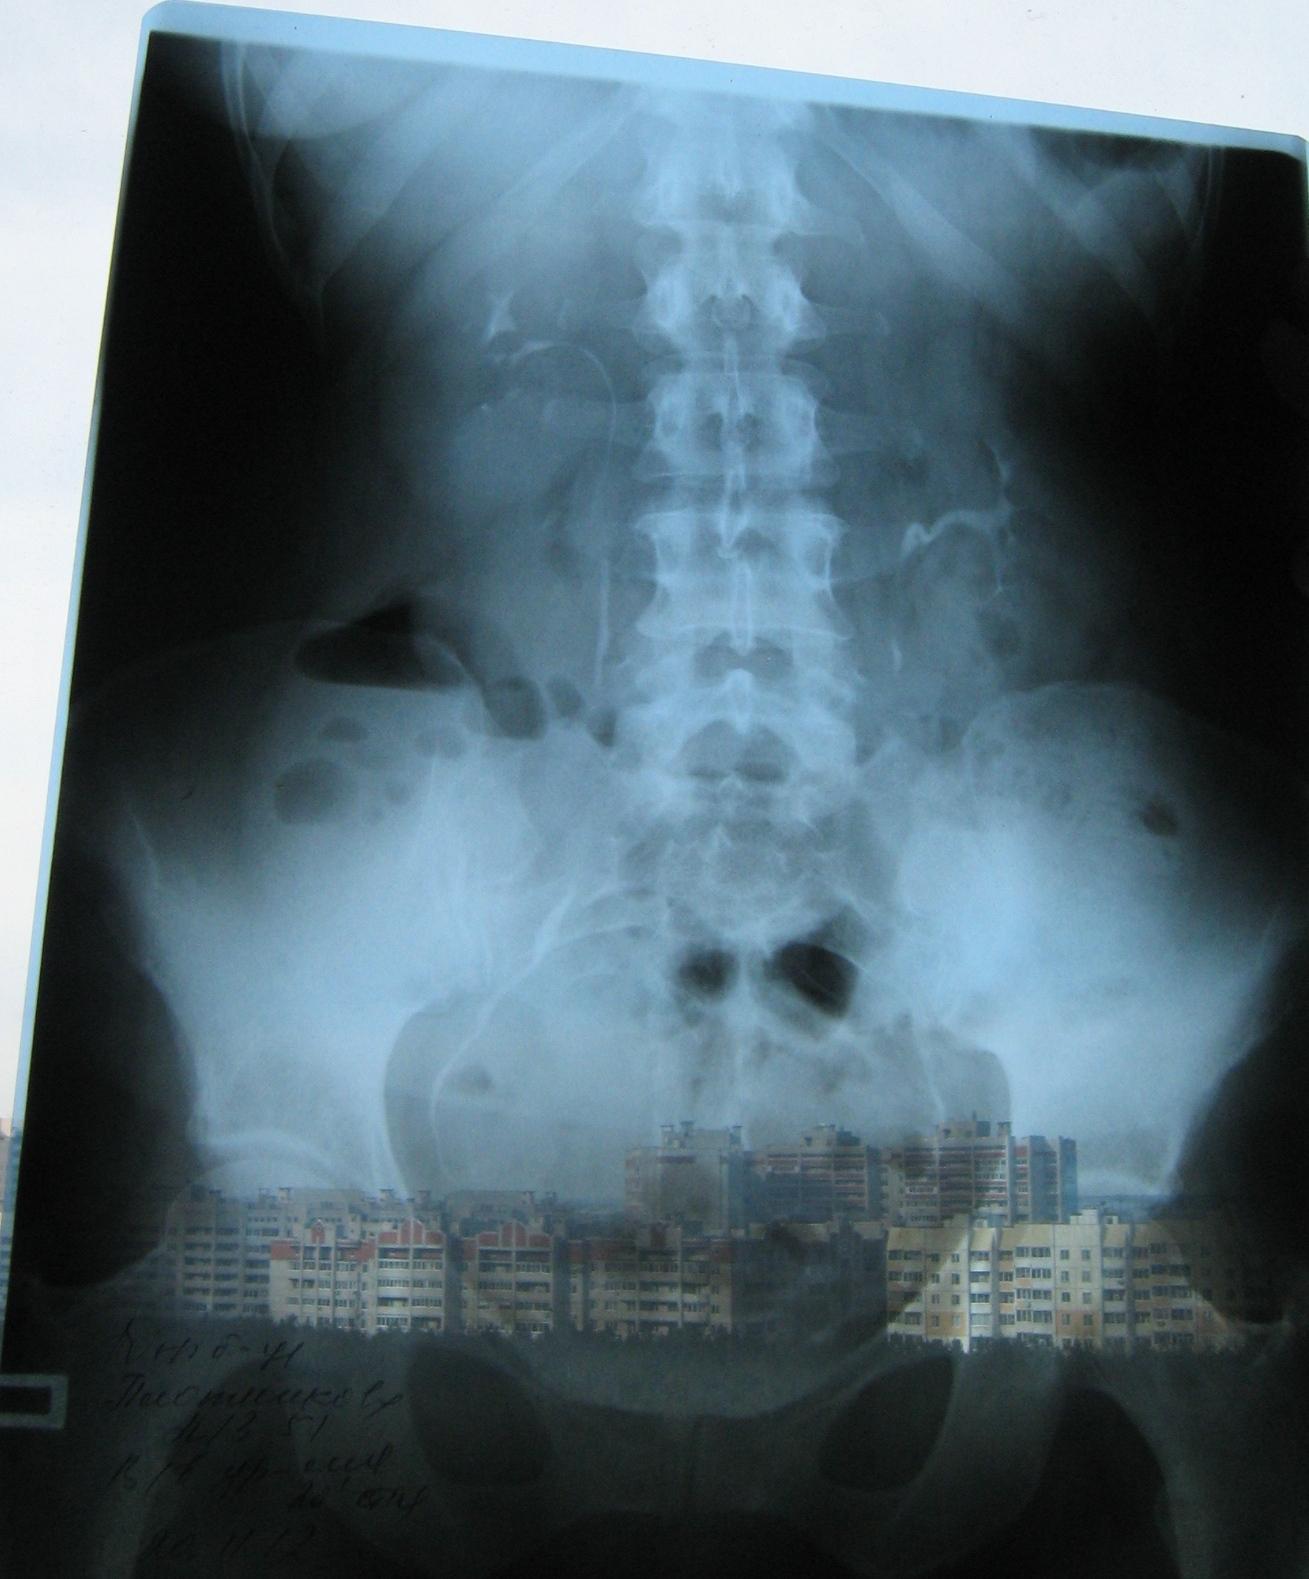

Была сделана операция 04.07.2012г по поводу нефропексии правой почки поясничной мышцей с помощью разреза. После операции болит правая сторона живота и в спине и в пояснице был затронут нерв, и до сих пор правая нога до колен не отходит спереди и сбоку. Через полтора месяца после операции образовался отек, пошло воспаление сзади на спине, потому что был затронут нерв. Сделала урографию через 4 месяца после операции. Если вас не затруднит, посмотрите пожалуйста снимки, правильно ли располагается мочеточник правый после операции. Скажите пожалуйста, посмотрев мои снимки, правильное ли расположение мочеточника и почему болит правая сторона живота все это время, и каким исследованием теперь после операции проверить что там творится в животе, что там затронуто? Все указывает на то что был затронут нерв, оперирующий врач говорит что не может быть такого, а я уже почти всю ногу правую не чувствую

Снимки прикрепляю